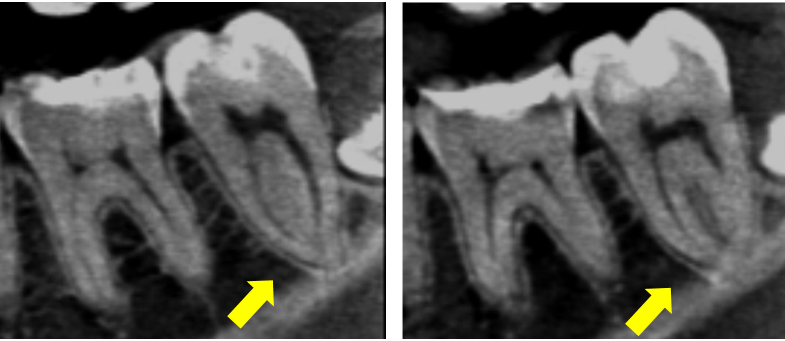

Ryc. 8. Przekroje strzałkowe drugiego zęba trzonowego żuchwy z kanałem typu C (strzałka żółta)